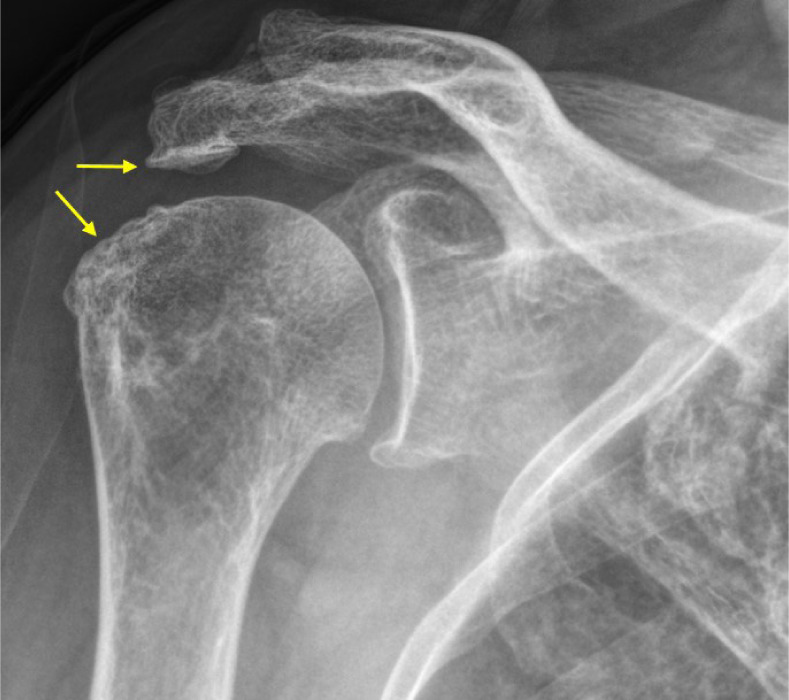

本综述的目的是为老年肩部疾病患者,特别是肩袖撕裂和骨关节炎的治疗提供一个全面的指南,并探索有效的非手术治疗方案。慢性肩袖撕裂通常是退行性的,而急性撕裂是由外伤引起的。这些撕裂的一个关键特征是肌腱变性伴有III型胶原蛋白优势,易使撕裂进展。肱骨关节的骨关节炎是由损伤软骨完整性的磨损变化引起的,导致疼痛和活动受限。准确的临床评估和成像,包括x线平片、超声和MRI,有助于诊断和指导治疗。体格检查强调活动度、肩袖强度和肩胛骨稳定性。治疗策略优先考虑缓解疼痛、保持功能和改善活动能力。非手术方式,包括运动、手工治疗和活动调整,是一线治疗方法,特别是对老年人。药理学方法包括非甾体抗炎药、皮质类固醇注射和神经性止痛药。类固醇注射有短期的好处,但反复治疗可能会损害组织的完整性。富血小板血浆是一种可促进肌腱愈合的再生选择,但结果不一,需要进一步研究。一个结构化的物理治疗方案,重点是活动范围和加强是必不可少的,与替代干预的明智使用。如果非手术方法不成功,应告知患者有关撕裂的潜在进展和未来可能需要手术干预的情况。包括关节活动和个性化运动方案在内的多模式方法,具有优化老年人功能结果和支持老年人独立的潜力。

The purpose of this review is to provide a comprehensive guide for managing older adult patients with shoulder diseases, specifically rotator cuff tears and osteoarthritis, and to explore effective nonsurgical treatment options. Chronic rotator cuff tears are typically degenerative, whereas acute tears result from trauma. A key feature of these tears is tendon degeneration accompanied by type III collagen predominance, predisposing tears to progression. Osteoarthritis in the glenohumeral joint arises from wear-and-tear changes that compromise cartilage integrity, leading to pain and restricted motion. Accurate clinical assessment and imaging, including plain radiographs, ultrasonography, and MRI, facilitate diagnosis and guide treatment. The physic-al examination emphasizes range of motion, rotator cuff strength, and scapular stability. Management strategies prioritize pain relief, function preservation, and improving mobility. Nonsurgical modalities, including exercise, manual therapy, and activity modification, constitute first-line treatments, especially for older adults. Pharmacological approaches involve NSAIDs, corticosteroid injections, and neuropathic pain medications. Steroid injections have short-term benefits, but repeated treatments may compromise tissue integrity. Platelet-rich plasma is a regenerative option that may improve tendon healing, but mixed findings highlight the need for further investigation. A structured physical therapy program focusing on range of motion and strengthening is essential, with alternative interventions used judiciously. Patients should be counseled regarding the potential progression of tears and the possible need for future surgical intervention if nonsurgical methods are unsuccessful. Multimodal approaches, including joint mobilization and personalized exercise regimens, hold potential for optimizing functional outcomes and supporting independence in older adults.